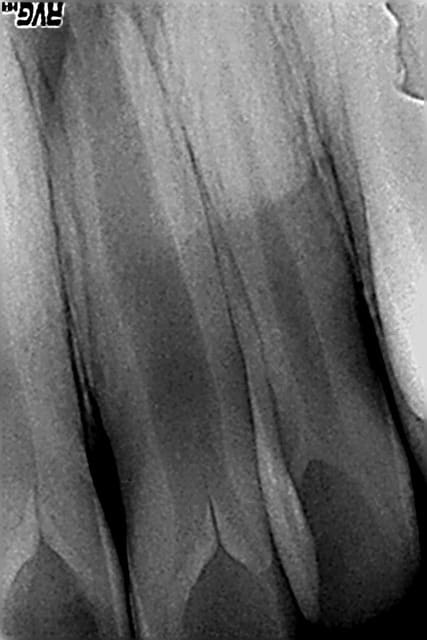

Cas clinique loin d'être parfait et je n'en était pas très fier :

12 ans

Traitement réalisé au MTA, j'ai merdé dans le placement du MTA comme on peut le voir sur la radio...

Radio 1 an post op : cicatrisation osseuse, plus de symptômes et pas d'inflammation particulière autour du MTA. Les parents sont prévenus que si ça pose problème on y retourne en chir.

PS : Ce n'est pas moi qui gère la prothèse, les parents n'ont pas donné suite au traitement coronaire proposé par leur dentiste... dommage